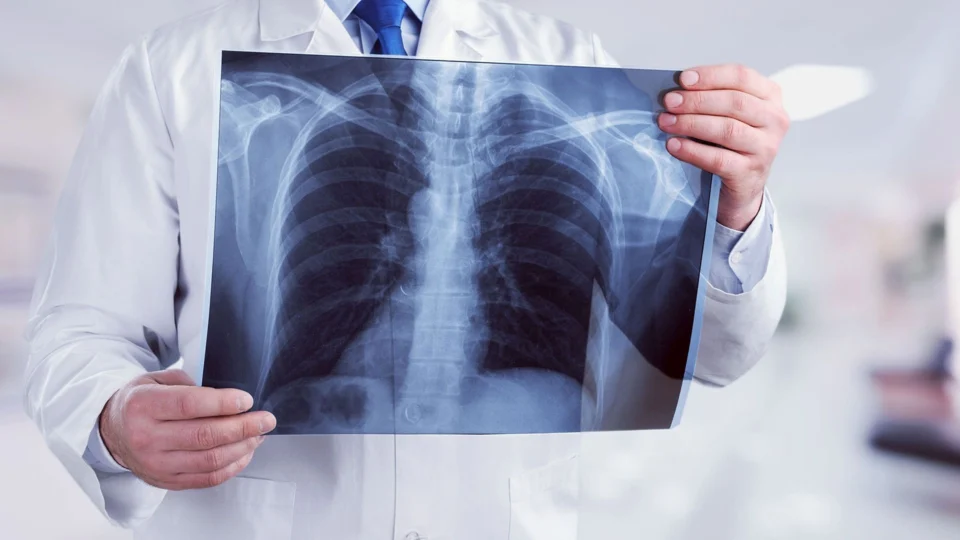

Causas e tratamentos da pnemonia

A pneumonia é uma doença aguda, tratável e curável. O médico pneumologista David Luniere explica sobre as causas e tratamento da doença.

“A Pneumonia é uma infecção do sistema respiratório inferior e os principais sintomas são tosse, febre, falta de ar, dor e desconforto torácico da localização no pulmão. Essa tosse pode ser seca e/ou com expectoração”, disse Luniere.

O doutor David Luniere reforça que a pneumonia também oferece riscos a quem teve Covid.

“Pacientes pós-Covid, que ainda tinham em seu pulmão alteração anatômicas devido à injúria causada pela Covid-19 e quando não se cuidavam ou se expunham a situações secundárias. Inclusive, era [a pneumonia] causa número um de reinternação.